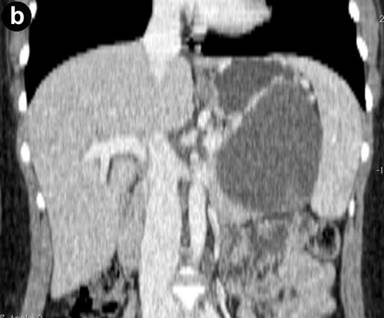

Abdominal US revealed an 8 cm anechogenic mass in the pancreatic tail. Abdominal CT scan was performed using a multi-detector 64 slices CT scanner (Aquilion, Toshiba, Tochigi, Japan) to confirm US findings; unenhanced CT scans showed a well-circumscribed cystic lesion, measuring 8x10 cm in pancreatic tail, with homogeneous low density; an internal this septum was present within the lesions. A contrast-enhanced acquisition was subsequently performed after i.v. bolus (3 mL/sec) injection of 120 mL of a non ionic iodinated contrast agent (Ultravist 370 mgI/mL, Bayer-Shering Pharma, Berlin, Germany) with a scan delay of 120 seconds; an automated dose modulation was used; the cyst wall and the internal septum showed a slight contrast enhancement (Figure 1); the stomach, spleen and left kidney were displaced by the mass. Further diagnostic investigation included a MR scan that was carried out using a 3T MRI (Gyroscan, Philips, Eindhoven, Germany) acquiring axial and coronal T1- and T2-weighted images with and without fat saturation integrated with MRCP T2-weighted hydro-cholangiographic sequences. In particular, the lesion was hyperintense on T2-weighted MR images (Figure 2) and homogeneously hypointense on the pre-contrast T1-weighted MR images showing a mild rim of enhancement after intravenous contrast administration (gadolinium diethylenetriamine pentaacetic-acid) in a volume of 20 mL with 2 mL/s) while maintaining the hypointensity of the central core constant; an internal septum of slight hyperintensity was present within the lesion, that was divided in two parts (Figure 3); MR cholangiopancreatography showed no communication between the lesion and the main pancreatic duct (Figure 4).

Figure 2. T2-weighted coronal MR image showed a simple cystic mass of the pancreatic tail displacing laterally the spleen; the thin line of hypointensity due to internal septum is clearly detected. |

The macroscopic characteristics of true cyst can be well demonstrates on US, CT and MRI images and allow a differential diagnosis with other cystic lesion of the pancreas [19]. In particular, CT and MRI showed in our case a well defined round mass, thin walled with an internal septum that showed a mild rim of enhancement after intravenous contrast administration; both on CT and MRI there was no solid component or central-cyst wall calcification. In this regard, the correct preoperative differential diagnosis based on imaging findings is a crucial point to select the most appropriate treatment, but it remains a very difficult issue; in particular, a true cyst of the pancreas should be differentiated, mainly, from neoplastic or non-neoplastic cysts. From a radiologic point of view an unilocular macrocystic lesion is indicative of pseudocyst in patient with a history of pancreatitis and/or serum amylase increase or for a true pancreatic cyst; conversely, the presence of the internal septum, is suggestive of a neoplastic nature in particular of intra-papillary mucinous neoplasm, when there is communication between the cyst and the main pancreatic duct, or mucinous cystadenoma [19]. In our case, on the basis of the sex and age, as well as the morphological and imaging findings, the hypothesis of mucinous cystadenoma of the pancreatic was made, but, a true pancreatic cyst was histologically demonstrated; however, the evaluation of the content of the cyst by fine needle aspiration was not available since it was not performed.